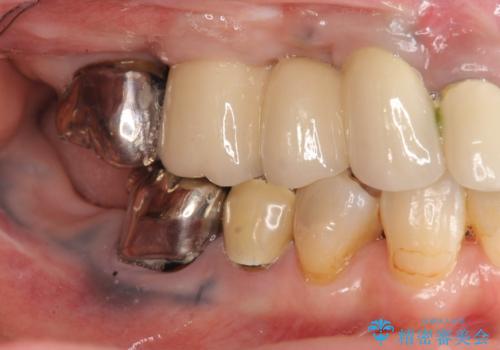

・再発した虫歯

・銀歯の下にできた虫歯

・根尖性歯周炎

・残根状態の歯

など、虫歯を原因とする問題が多発した状態です。

今後延々と治療を繰り返さないために、全ての銀歯を外し虫歯を丁寧に取り切り、根管治療を行い、残せない歯は抜去を行った上でインプラント治療を行っていくことで全体的な治療を計画していくこととなりました。